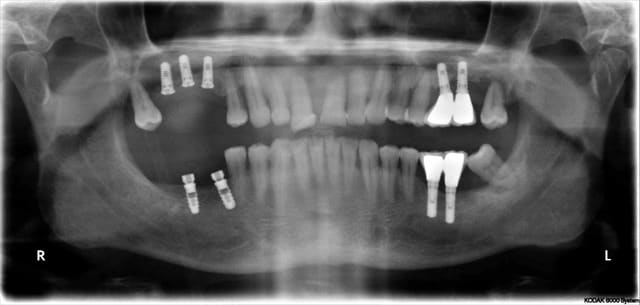

Vous regardez un cas de mci et ne voyez que l’implant sur 9 (je ne parle pas des derniers qui n’ont que quelques jours) qui posé il y a 4 ans lors d’un sinus lift latéral ne va pas bien, et de 2 (8) qu’un 3ème année pourrait enlever.

Ce patient arrivant aujourd’hui en consultation avec la pano initiale, je dirais aussi que mon protocole est nul et il n’a que 4 ans.

Aujourd’hui le protocole serait scanner, discussion avec mes associés paro et ortho, et probablement exo, Mci sans sinus lift.